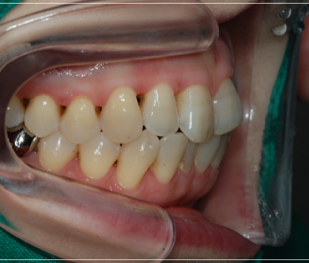

이 처럼 입을 다물어도 어금니만

맞물린 채 앞니가 맞물리지 않는 증상을

개방교합이라고 부르는데요.

개방교합은 입을 다물때 안쪽

어금니만 맞닿고 앞니 쪽은 닿지 않아

입술이 붕 떠 있는 상태를 말했어요.

성장 중의 부정적인 문제로 인해

발생한 개방교합은 보통 치아를

교정하면 위와 같은 불편함이 해결 될

것이라고 생각하시는 분들이 많은데,